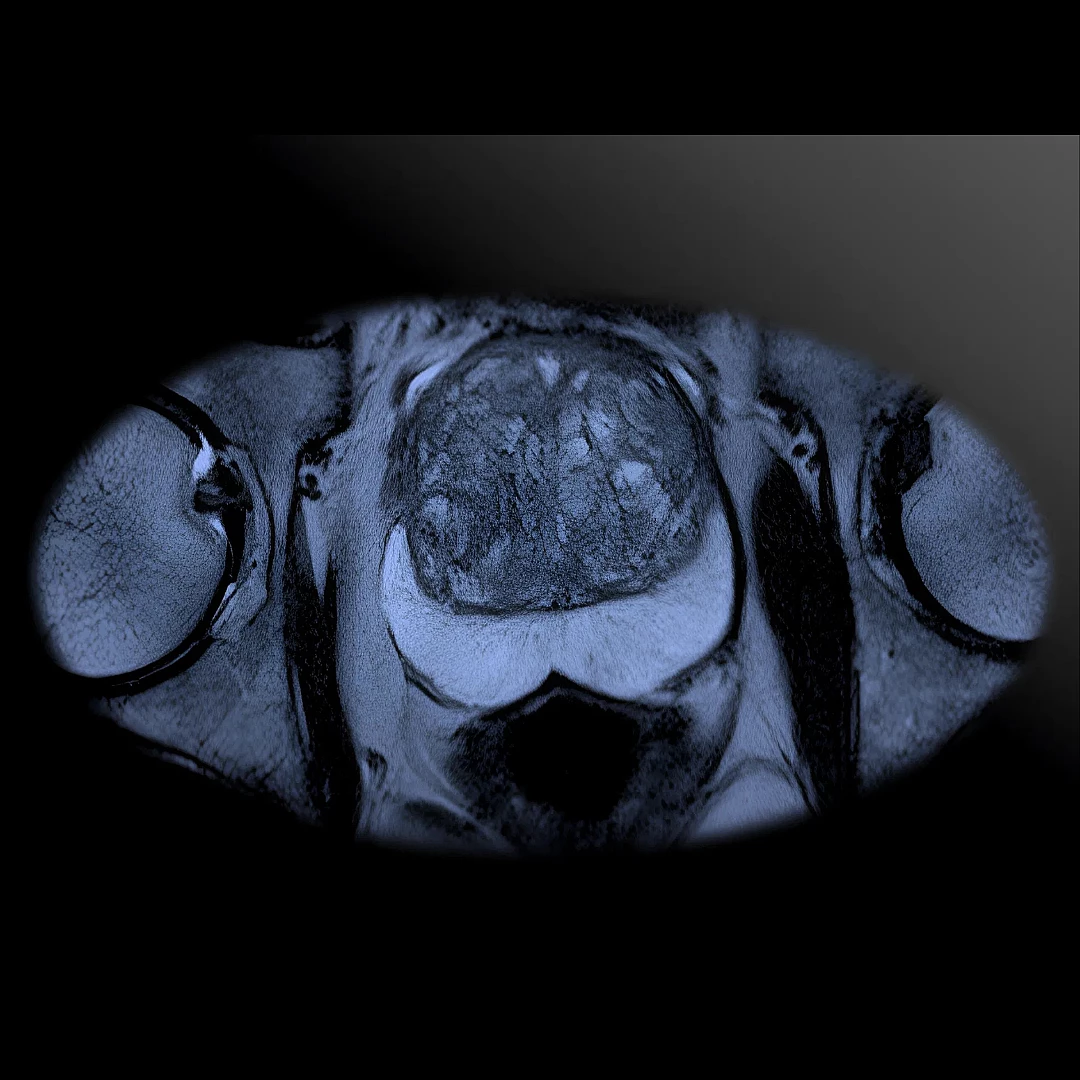

Prostate MRI delivers high-resolution images of the prostate gland to detect tumors, assess cancer risk, or guide biopsies. It’s a non-invasive, radiation-free tool for accurate diagnosis and treatment planning in men’s health.